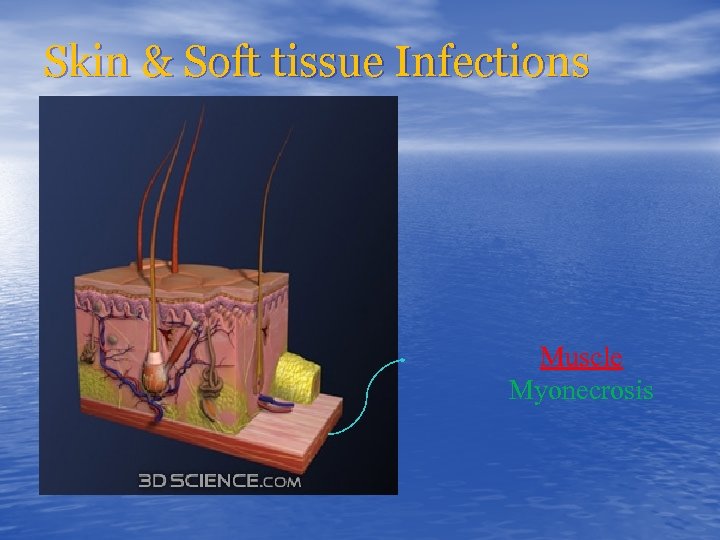

Skin & Soft tissue Infections Muscle Myonecrosis

Skin & Soft tissue Infections Muscle Myonecrosis